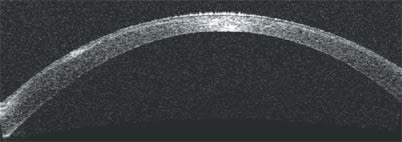

Depicting density, the color version of the anterior-segment scan shows lower amplitudes as blue colors and larger amplitudes as red colors.

The color version of the high-resolution corneal scan shows the useful light coming through the implant's aperture and the scattered light coming through the implant's fenestrations.

The Visante OCT also is proving to be useful in association with intracorneal refractive implants. The OCT images on this page depict an ultra-thin intracorneal implant currently being evaluated in patients for the correction of presbyopia (AcuFocus Inc.). Based on small-aperture optics, an optimized pinhole, the implant is 3.80 mm in diameter and has a 1.60-mm aperture.

The Visante OCT's high-resolution corneal scan and anterior-segment scan pinpoint the location of the implant and allow measurement of its diameter and thickness.

As this implant was being developed, the Visante OCT allowed documentation of the amount of scattered light coming through the implant's fenestrations. This allowed researchers to determine what level of light passing through caused glare and reduced contrast and what level did not affect patients' contrast sensitivity. OM